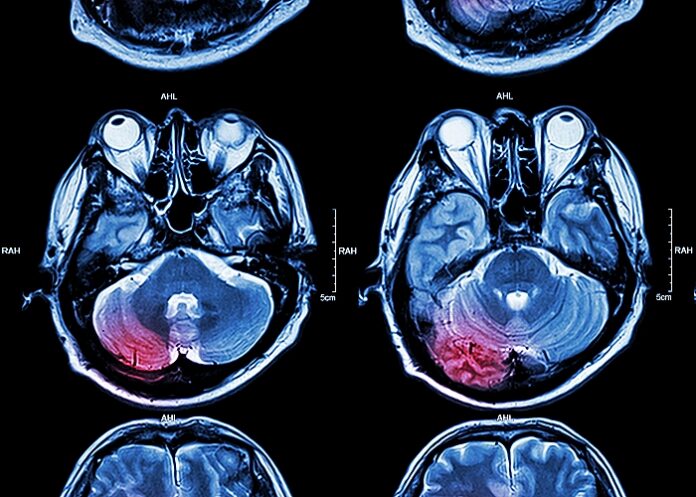

The research analysed patterns in patients who suffered ischaemic stroke, the most common type of stroke, which occurs when a blood clot blocks or narrows an artery leading to the brain, and also intracerebral haemorrhage, which is less common and involves bleeding within the brain tissue itself.